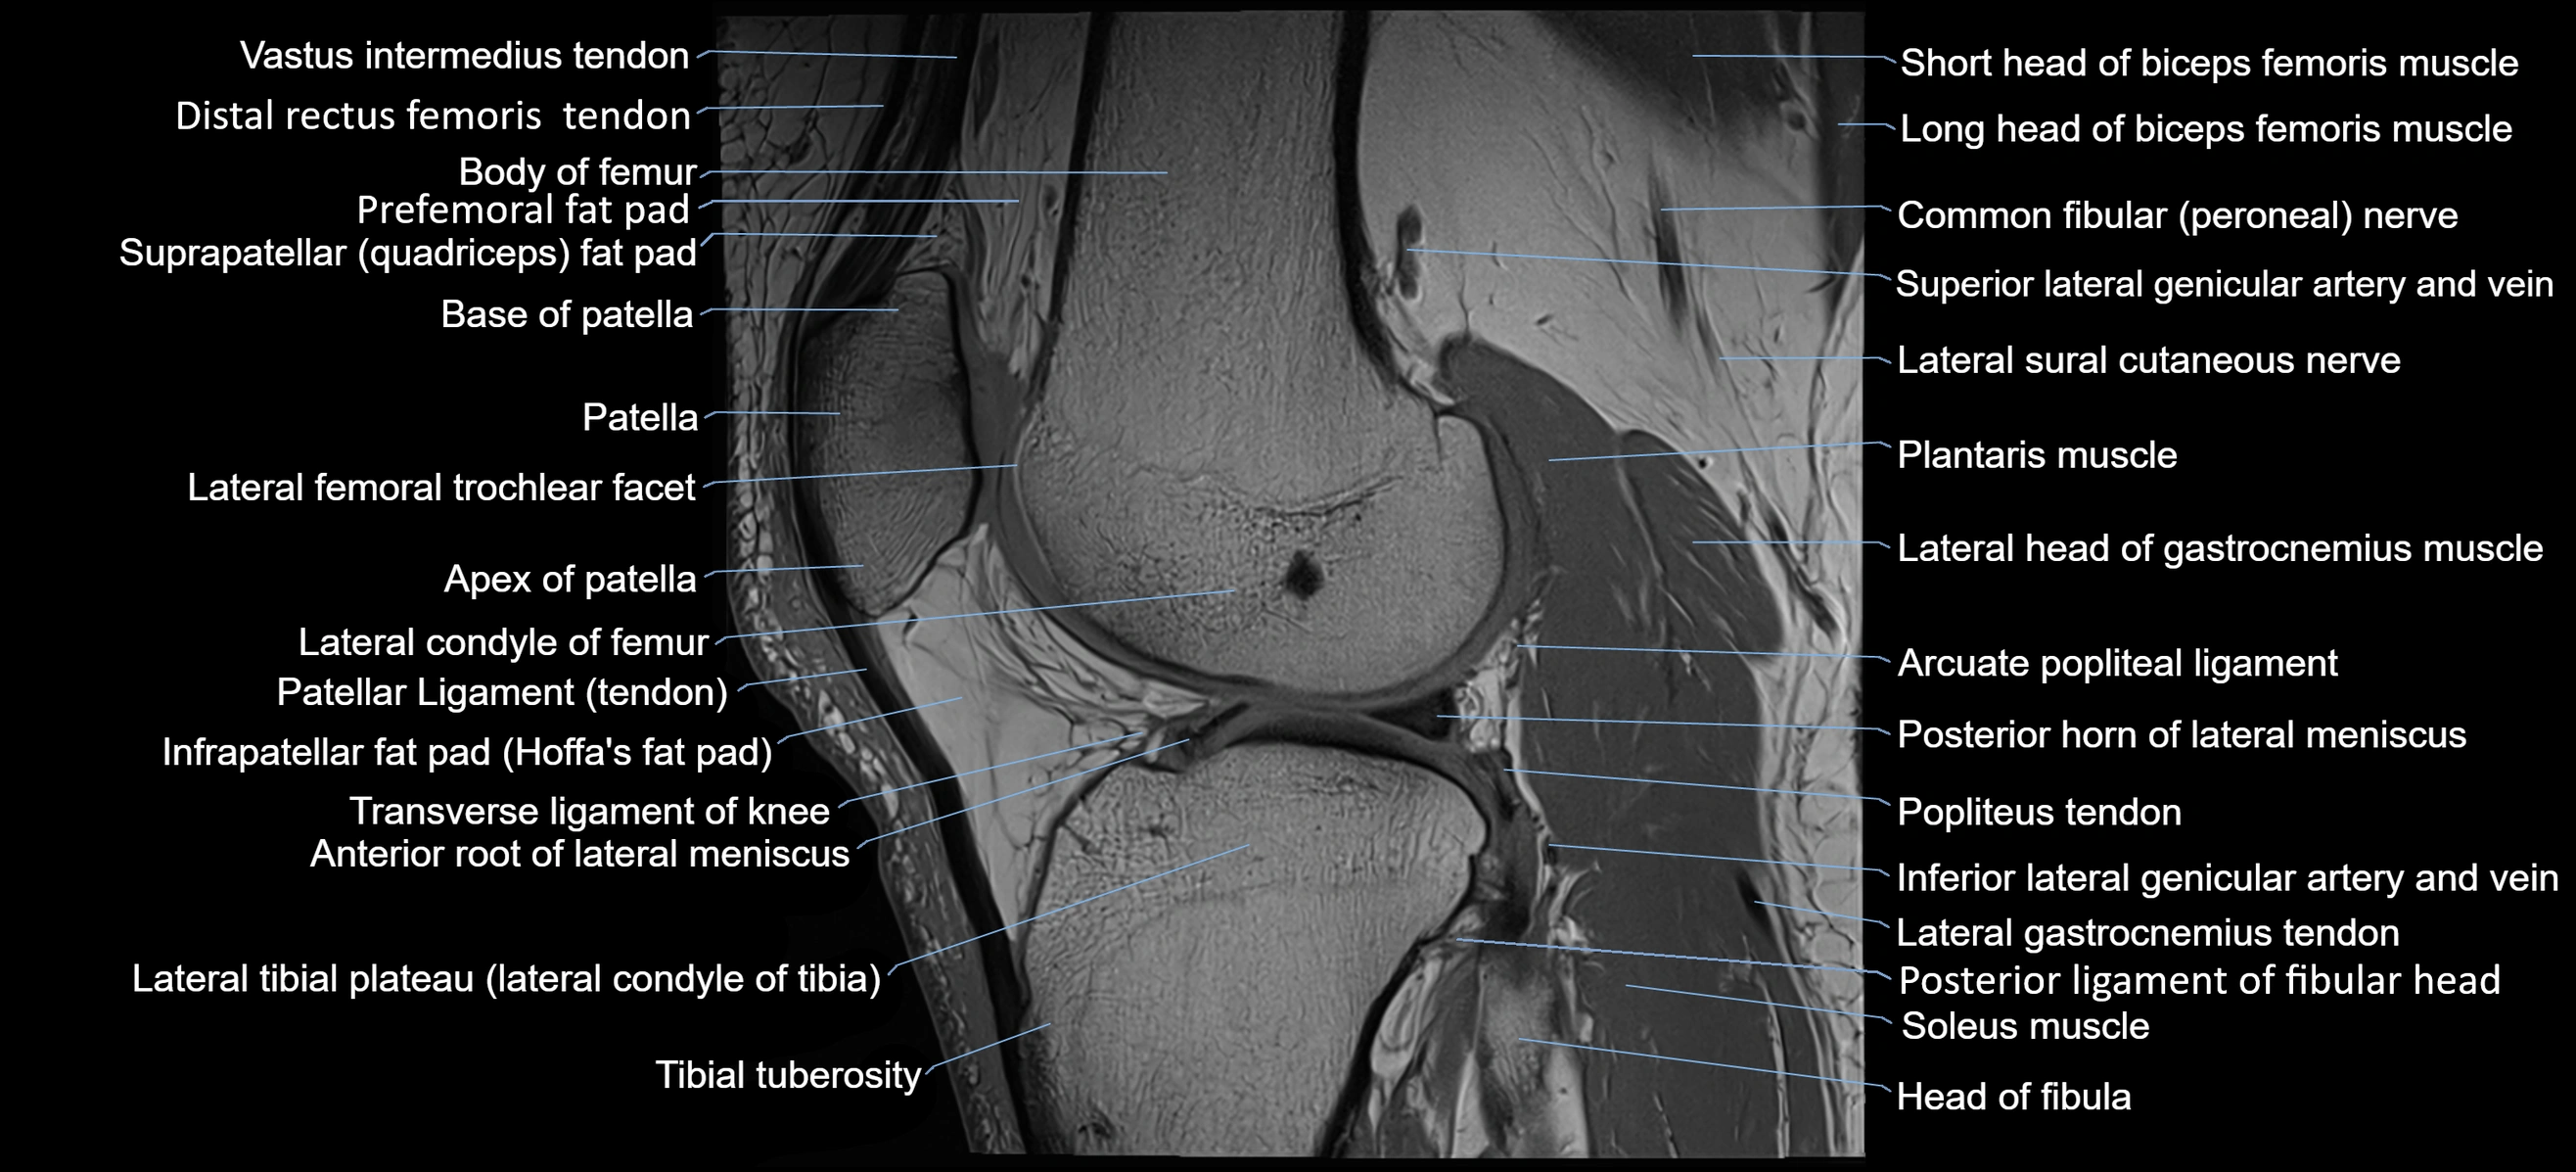

- Anterior root of lateral meniscus

- Apex of patella

- Arcuate popliteal ligament

- Base of patella

- Biceps femoris muscle (Short head)

- Body of femur

- Common fibular nerve

- Distal rectus femoris tendon

- Distal vastus intermedius tendon

- Distal vastus lateralis tendon

- Head of fibula

- Infrapatellar fat pad

- Lateral condyle of femur

- Lateral gastrocnemius tendon

- Lateral head of gastrocnemius muscle

- Neck of fibula

- Patellar tendon (patellar ligament)

- Plantaris muscle

- Popliteus tendon

- Posterior horn of lateral meniscus

- Posterior ligament of fibular head

- Prefemoral fat pad

- Soleus muscle

- Superior lateral genicular artery

- Superior lateral genicular vein

- Suprapatellar fat pad

- Tibial tuberosity

- Transverse ligament of knee

- Trochlear groove